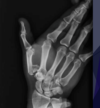

Fratura de Chaffeur

Fratura do processo estilóide do rádio.